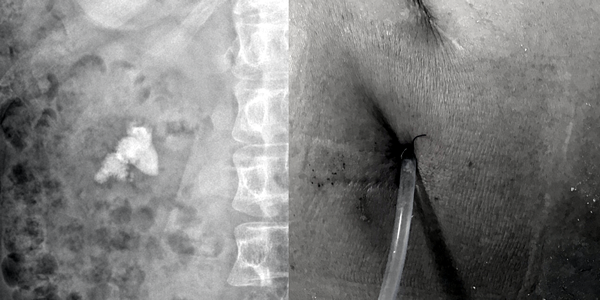

Sỏi thận ở bệnh nhân quan sát được qua phim X-Quang

Sỏi bệnh nhân quan sát qua Xquang được lấy ra khỏi cơ thể với vết mổ chưa đến 1 cm

Sau khi xác định tình trạng sỏi hiện tại của BN phù hợp để điều trị bằng tán sỏi qua da đường hầm nhỏ (mini – PCNL), phương pháp hiện đại nhất hiện nay trong việc điều trị sỏi thận, sỏi đường tiết niệu. Thông qua một đường hầm nhỏ 18Fr (tương đương 0,6 cm) được tạo từ hông lưng bệnh nhân vào thận, dưới sự dẫn đường của sóng siêu âm, tia Holmium laser (laser công suất lớn) sẽ tán nhỏ, làm sạch và đưa sỏi ra khỏi cơ thể trong một lần điều trị. Sau cuộc nội soi kéo dài 90 phút, bệnh nhân được chuyển về phòng hồi sức, tình trạng sức khỏe ổn định và xuất viện sau 3 ngày.